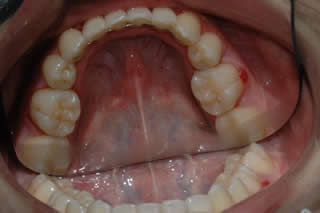

Lower Incisor Crowding:

Late lower incisor crowding is a very common problem.

3 - 9 months of treatment can correct the mild-moderate lower incisor crowding.